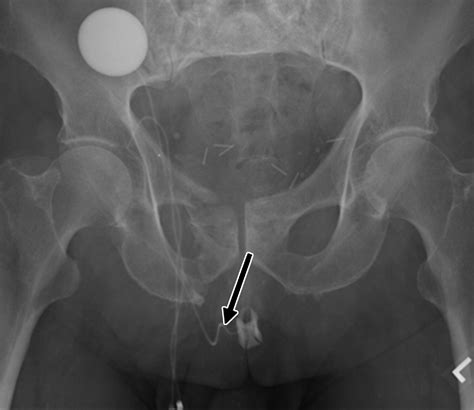

An Artificial Urethral Sphincter is a surgically implanted device designed to mimic the function of the natural sphincter muscle, which normally keeps the urethra closed to prevent urine leakage. When this natural muscle is damaged or weak, the AUS takes over the responsibility of controlling the flow of urine. The device is entirely contained within the body, making it discreet and effective for long-term use.

The system typically consists of three interconnected components:

• The Cuff: A circular balloon placed around the urethra that inflates to keep the urethra closed.

• The Pump: A small control mechanism placed in the scrotum (for men) or labia (for women) that allows the patient to manually deflate the cuff when they need to urinate.

• The Balloon (Pressure-Regulating Reservoir): A reservoir implanted in the abdomen that regulates the pressure within the system to ensure the cuff stays closed yet comfortable.

• artificial urethral sphincter radiology